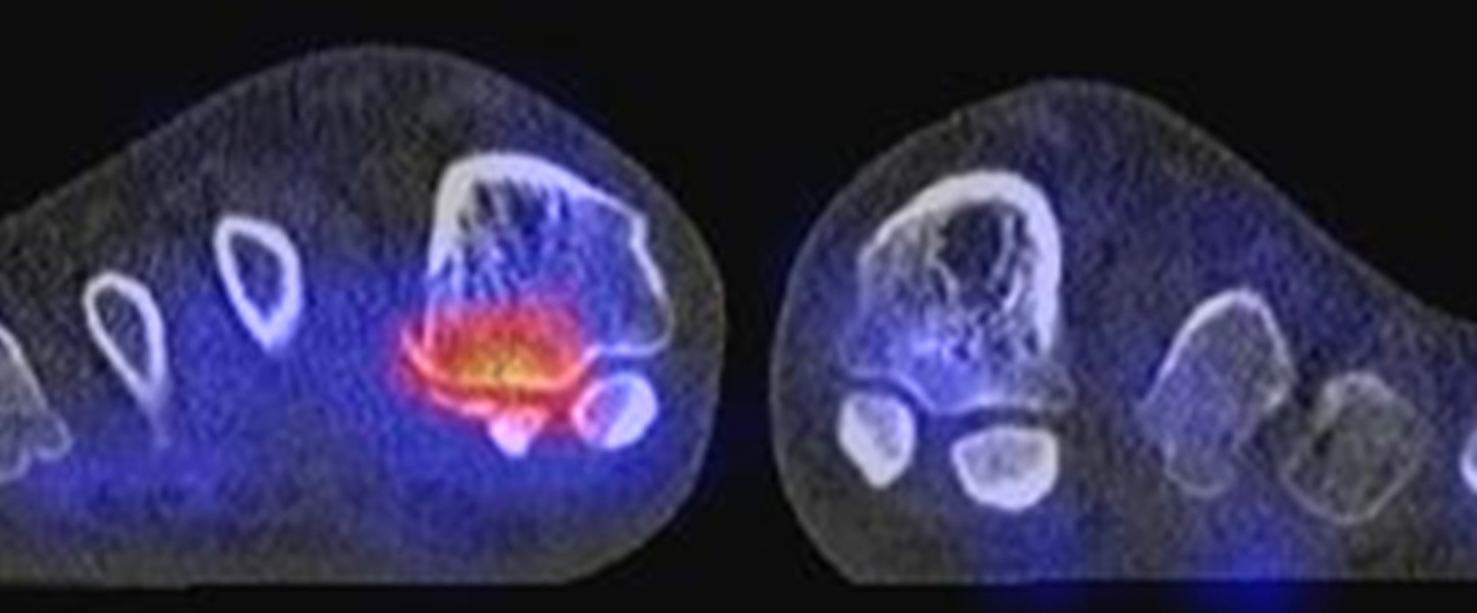

Bekannte Gicht mit Polyarthralgien. Am rechten Großzehengrundgelenk lateral in der Grundphalanx entzündliche Erosionen.

Gichtarthritis mit Osteolysen und flauen Verkalkungen in den periartikulären Weichteilen/Gelenkkapsel.